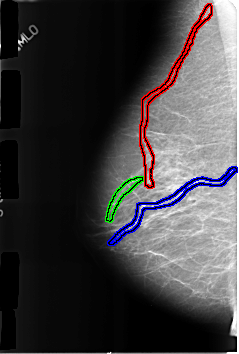

B_3170_1.RIGHT_MLO

FILE: B_3170_1.RIGHT_MLO.OVERLAY

TOTAL_ABNORMALITIES 3

ABNORMALITY 1

LESION_TYPE CALCIFICATION TYPE VASCULAR DISTRIBUTION N/A

ASSESSMENT 2

SUBTLETY 3

PATHOLOGY BENIGN_WITHOUT_CALLBACK

TOTAL_OUTLINES 1

BOUNDARY

ABNORMALITY 2

ABNORMALITY 3